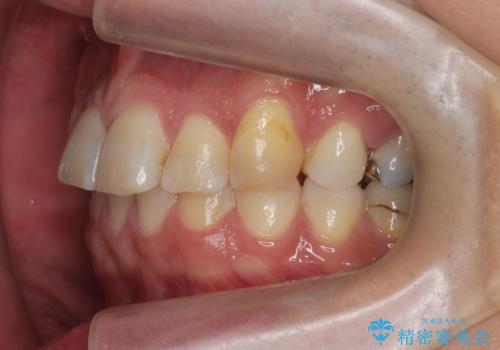

上の前歯が斜めに見えること、犬歯と小臼歯の間の隙間、上下顎前歯のがたつきを治すことをご希望されていました。

ご予算と患者様のご希望により、インビザライン・ライト(マウスピース14枚)によるマウスピース矯正を行いました。